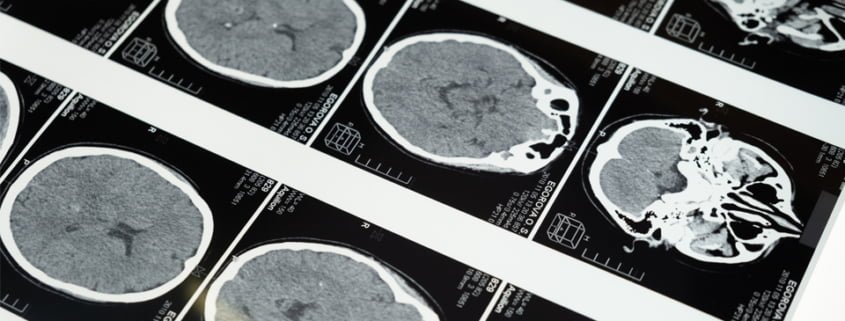

⦁ MR’ın MS’i desteklemesi (Barkhof, KIDMUS, Callen Kriterleri ile) MS tanısını koymak için olması gereken şartları göstermektedir.